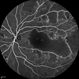

- capillary closure, macular infarction

- Wide-field FA image of the left eye of a 28-year-old woman with idiopathic occlusive retinal vasculitis 6 months after the onset.